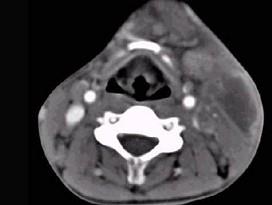

问题 男性,67岁,颈部出现疼痛性肿块半年余,CT扫描如图所示,最可能的诊断是 ( )

选项 A、淋巴瘤 B、血管瘤 C、囊肿 D、淋巴结核 E、神经鞘瘤

答案 A